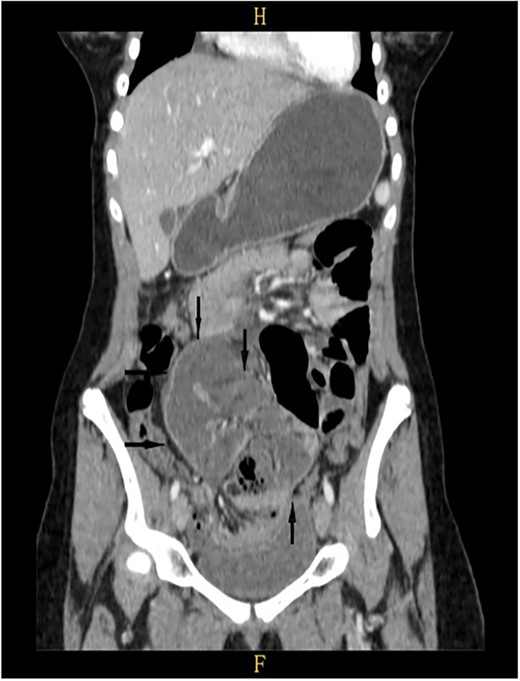

On a retrospective review of our patient’s ECT, we recognised a membrane encapsulating the small intestine centrally, which indicates the diagnosis of ACS (Figs 4 and 5).

Retrospective review of ECT (axial section), a membrane encapsulates the small intestine centrally indicates the diagnosis of ACS (black arrows).

Retrospective review of ECT (coronal section), a membrane encapsulates the small intestine centrally indicates the diagnosis of ACS (black arrows).